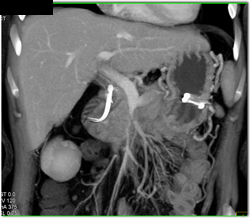

Pseudocyst